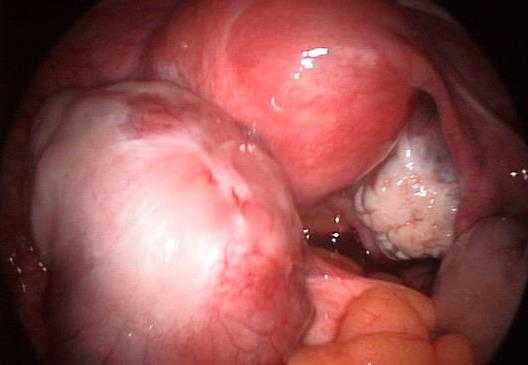

Гиперпластические и воспалительные новообразования яичников являются доброкачественными. Неопластические опухоли могут переродиться в злокачественные. Посмотреть, как выглядят различные виды полипов яичников можно на фото.

Для получения доступа к яичникам проводят лапароскопию. При ее проведении врач может увидеть все новообразования на яичниках и удалить их. После операции извлеченные ткани отправляются на гистологию. Этот вид обследования дает возможность узнать, доброкачественная или злокачественная опухоль была в организме.